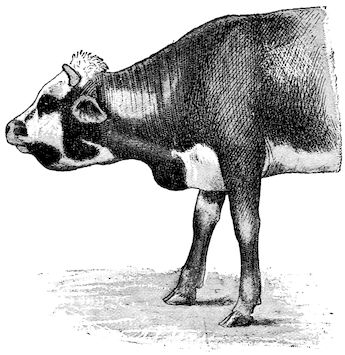

Fig. 2.—Horse suffering from osseous cachexia.

Fig. 3.—Pig suffering from osseous cachexia (fourth stage).

Such shocks would be of no importance to a healthy animal, but to one suffering from osseous cachexia, any violence, or even the slightest muscular effort may be followed by fracture of the gravest character, involving even the vertebral column. In cows the pelvis, femur, and tibia are most frequently injured.

In horses, particularly in riding horses, fractures are commonest in the region of the forearm, cannon bone, and anterior phalanges. So extremely fragile are the bones at this stage that the horse represented herewith broke twelve ribs at one time by simply falling on its side. It is interesting to note that such fractures are never accompanied by any extensive bleeding. They have little tendency to repair, no real callus formation occurs, and on post-mortem examination one often finds the ends unconnected by temporary callus, worn, and rounded by reciprocal friction.

At this stage but under other circumstances, the animals show great reluctance to rise, remaining down for twelve to twenty-four hours without shifting their position. If forced to get up, they stand as though fixed in one position, the respiration and circulation become rapid, and they soon grow tired and fall.

Fig. 6.—Osseous cachexia. This condition developed in two months, the last month of gestation and the first of lactation.